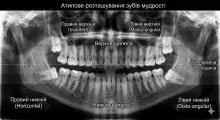

Зуби мудрості (вісімки, треті моляри) - останні чотири зуба в кожному кутку щеl